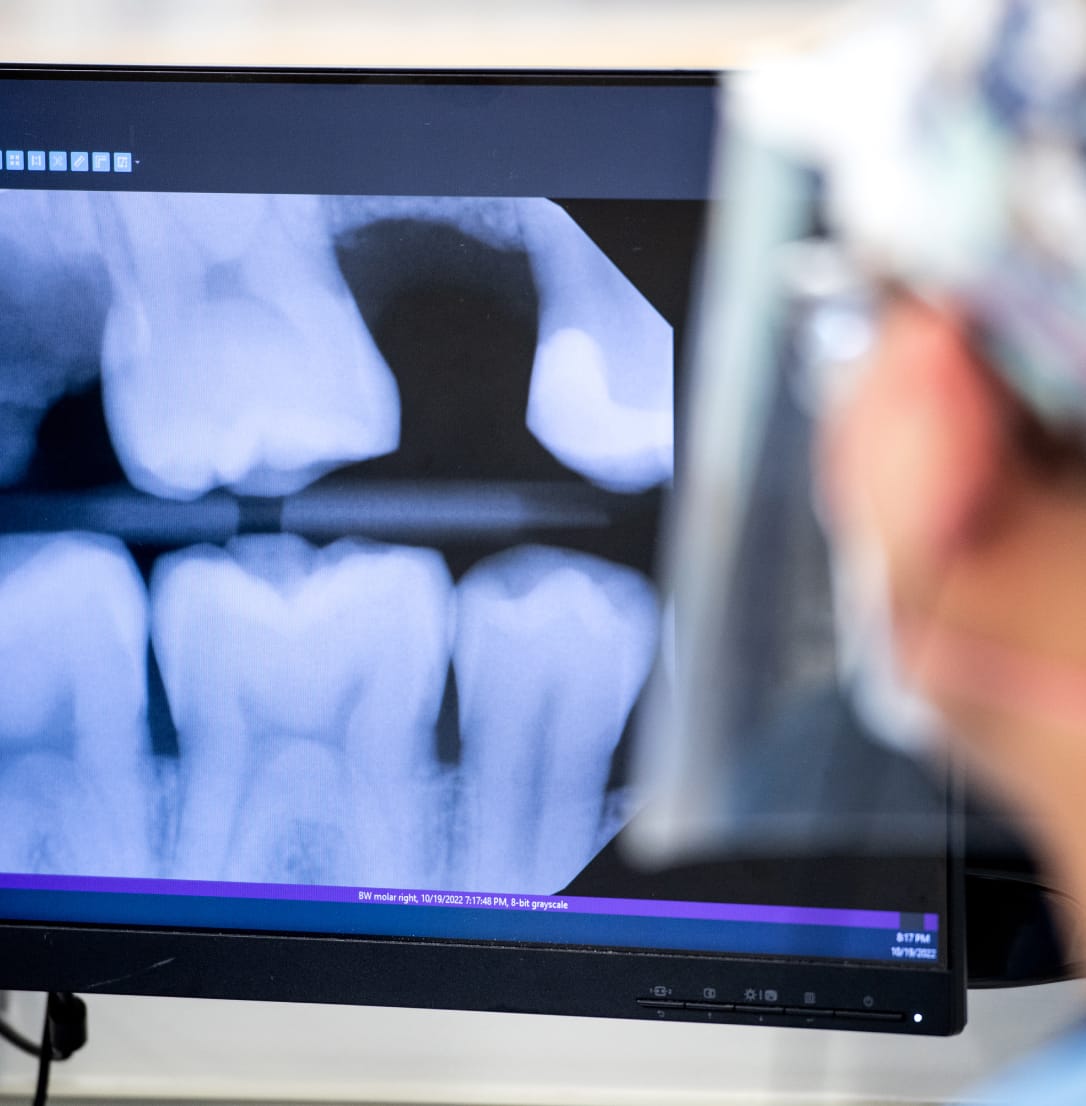

Your provider may suggest that you get X-rays as part of your exam. Dental X-rays are important because they help dentists detect problems that are not visible during a regular examination, such as cavities, gum disease, and issues with tooth roots. Despite their very low dose of radiation, they provide a comprehensive view of oral health, allowing for early diagnosis and treatment, which can prevent more serious dental issues later on.